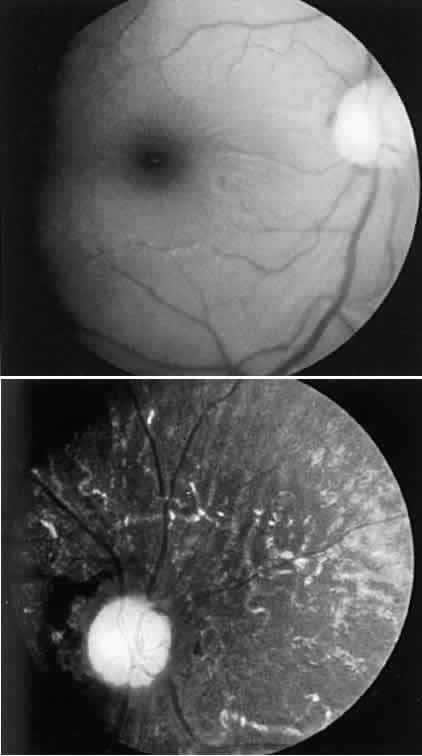

tests were normal. CASE 3 (FIG. 10). A 57-year-old female was referred because of increasing complaints of

difficulty with her night vision and her side vision. She had a long history

of low-grade uveitis and a progressive decrease in central vision. Visual

acuity 20/100 OD, 20/80 OS. The vitreous showed multiple small

cells. Both retinas showed narrowed arterioles and strands of pigment

in the far periphery. Multiple areas of atrophy of the RPE were seen

throughout. An ERG was extinguished.  Fig. 10. Case 3. Left. Posterior pole. Right. Peripheral retina. See text for details. Fig. 10. Case 3. Left. Posterior pole. Right. Peripheral retina. See text for details.

|

This patient had birdshot choroiditis, an inflammatory disorder of the

choroid with severe secondary photoreceptor degeneration. The ERG gives

evidence of widespread degeneration, but the history and clinical findings

preclude the diagnosis of a generalized heredoretinal degeneration. This

disorder of birdshot choroiditis may produce a “pseudo-retinitis

pigmentosa” picture8 (Table 2). TABLE 2. Pseudoretinitis Pigmentosa